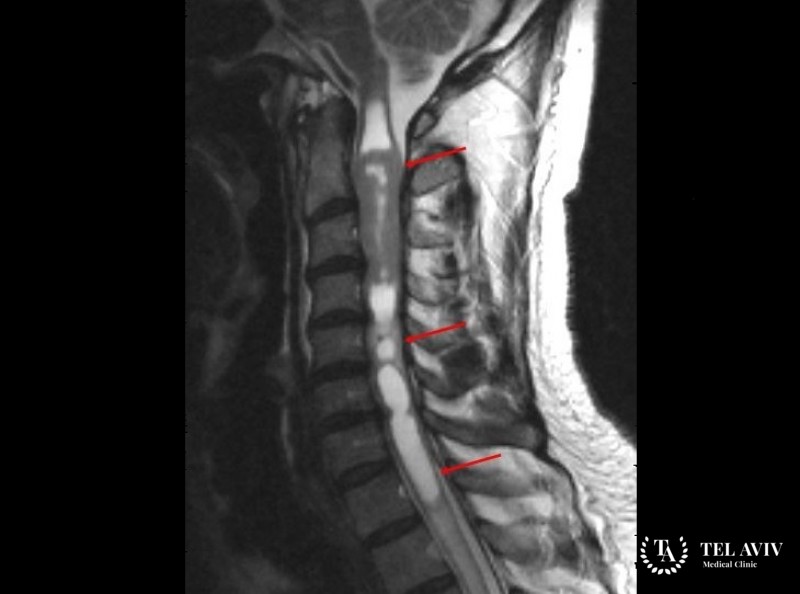

- Магнитно-резонансную томографию – для выявления формы, локализации, размеров патологии;